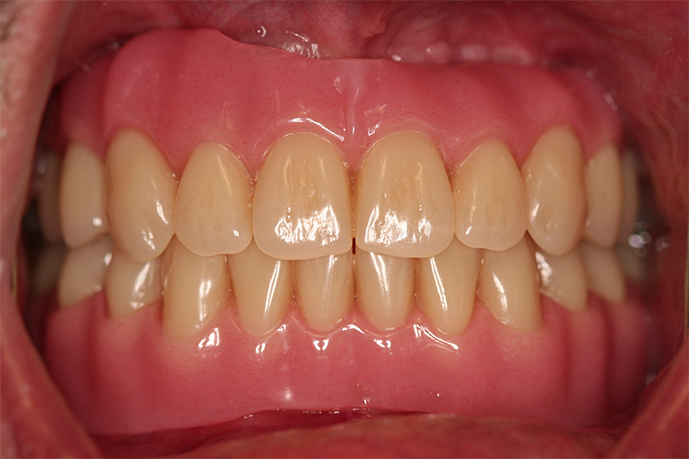

Paciente de 76 anos do sexo masculino

Motivo da consulta: Paciente desdentado total, procurava colocar dentes.

Plano de tratamento: Colocação de 4 implantes superiores e 2 implantes inferiores. Confeção de uma barra superior e colocação de 2 locators® na parte inferior. Confeção de uma prótese superior e outra inferior removível, com encaixes na barra e locators®.

A escolha deste plano de tratamento deve-se ao facto de o paciente querer uma solução total, mas não completamente fixa, uma vez que não tinha muita destreza manual para higienizar uma prótese fixa. Desta forma, conseguiu uma solução bastante retentiva (devido aos encaixes) mas que consegue remover para uma higienização correta.